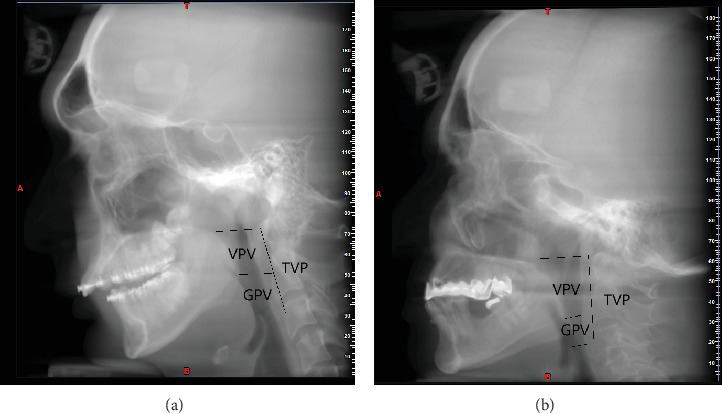

Aim: This study evaluated the relationship between airway volume and skeletal malocclusion. Methods: This study was a cross-sectional analytical study obtaining 450 cone-beam computed tomography (CBCT) images from the archives of a private clinic taken by the Sirona Galileos Comfort Plus, Dentsply Sirona, Germany device, following the Fast-Scan protocol with 14 s exposure time, FOV = 15 × 15 cm, kV = 98, and mA = 3. The CBCT images were from adults aged 17-39 years with a normal pattern in their vertical growth (SN-GO.GN = 32 ± 5), with no history of orthognathic or rhino surgery, no syndromes, no previous trauma, and no pathologies along the airway and pharynx detectable in the images. CBCT images with radiographical artifacts and low quality or resolution were excluded from the study. The total pharyngeal volume (TPV) was measured from the superior part of the PNS (posterior nasal spine) parallel to the standard horizontal plane to the anterior-inferior part of the C4 vertebra, parallel to the standard horizontal plane. Velopharynx volume (VPV) was measured from the superior part of the PNS to the inferior border of the soft palate. Glossopharynx volume (GPV) was measured from the inferior border of the soft palate to the superior tip of the epiglottis. The volumes were reported in mm3. To analyze data, SPSS version 22.0 (IBM Corp, Armonk, NY, USA) was used. ANOVA and Tukey's post hoc test were applied. Results: The results revealed that the mean total pharyngeal airway volume and velopharyngeal airway volume were significantly larger in Class III patients compared to Class II and Class I patients. Also, in Class I patients, the mean total pharyngeal airway volume and velopharyngeal airway volume were significantly greater than in Class II patients. The glossopharynx airway volume was significantly different between Class II and Class III patients, so the glossopharynx airway volume was significantly greater in Class III patients than in Class II patients. Conclusion: The results showed that there is a relationship between skeletal malocclusion and airway volumes.